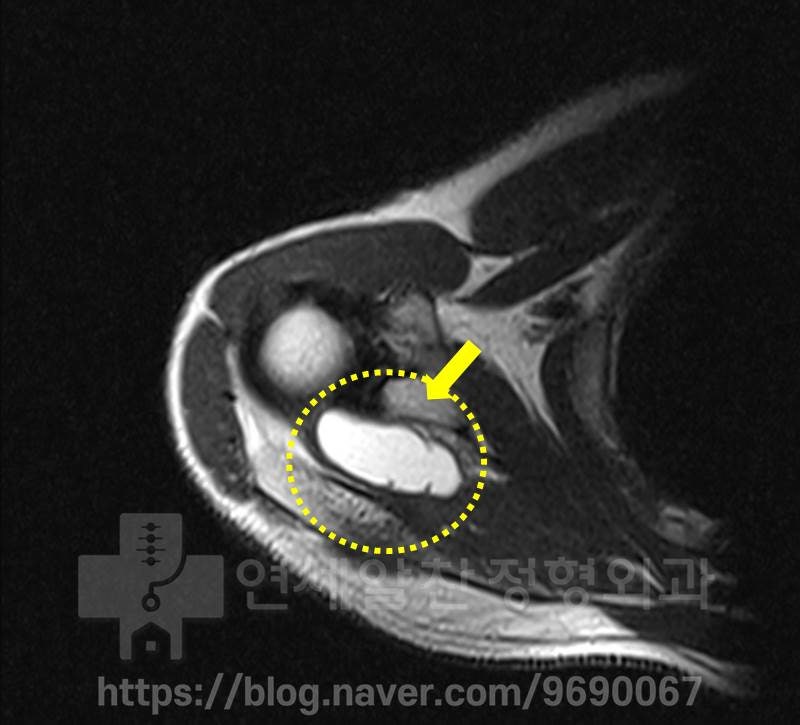

비슷한 위치로 다시한번 커다란 어깨물혹이 관찰되고 있으며 관절와순의 손상은 확인되지 않습니다.